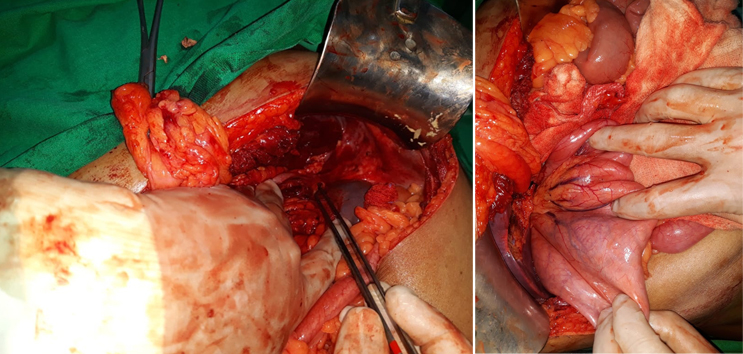

A Young lady who was a small kid...when her mother was operated for a Complex Gastrointestinal condition almost 14 years back by Dr Suddhasattwa Sen suddenly came in with severe blood loss from Gastrointestinal tract with a loss of almost 2 to 3 litres of blood with Shock with fainting . Further stabilisation was done and then extensive investigation revealed not only Piles and GI Ulcers but also SRUS Bleeding ulcers in rectum. A condition called Solitary Rectal Ulcer Syndrome ( a complex and difficult to cure anorectal problem ) . Her hemoglobin dropped to below 7 gm% She finally underwent surgery after 5 days and left home after 2 days post op without any further bleed or problems .